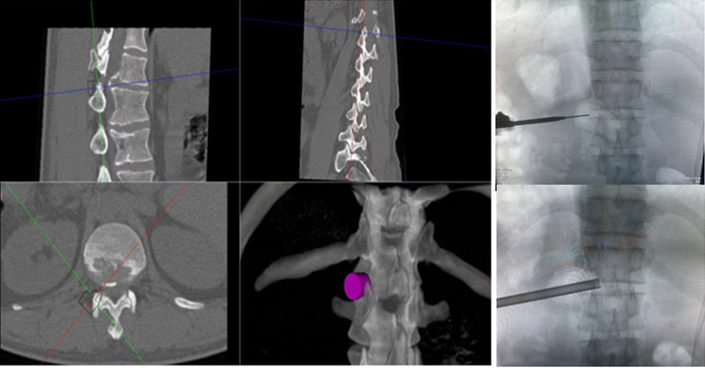

,均建议采取传统外科开放手术治疗,患者因担心手术风险,迟迟不愿手术。经多方打听,患者慕名找到李全义主任医师,李全义主任医师接诊后,仔细研究患者的疾病特点,腰椎间盘突出症常见于低位椎间盘(L4/5、L5/S1),而该患者属于高位椎间盘突出(胸12/腰1节段),并且已经引起了马尾综合征,表现为会阴部及鞍区疼痛、麻木、二便障碍,高位椎间盘突出因高位椎管不如低位椎管容积大,在穿刺时容易损伤神经,造成严重并发症。与患者经过充分的沟通,决定采用目前骨科前沿技术-----机器人辅助微创手术。在病院主任刘时璋教授的带领下,李全义主任医师团队顺利为患者实施ORTHBOT脊柱机器人辅助椎间孔镜下胸12腰1髓核摘除、椎管扩大减压术,手术在局部麻醉下进行,以机器人辅助微创手术解除了患者的痛苦,减少手术创伤及并发症,缩短手术时间。

椎间孔镜在治疗脊柱相关疾病方面,尤其在治疗腰椎间盘突出症,具有创伤小、恢复快、花费少、床位周转快等优点,但椎间孔镜在术中穿刺过程中,需要反复调整穿刺针位置,需要较多的透视,特别是高位椎间盘突出症患者,稍有不慎便引起严重并发症。骨科手术机器人利用术前患者的影像学资料,模拟建立穿刺路径及各项参数,能极大地优化手术方案使其更加精准、更加安全、更加有效,显著降低了在穿刺过程中反复操作给患者造成损伤,极大程度上有效避免了严重并发症的发生。

ORTHBOT脊柱机器人术前设计及术中穿刺